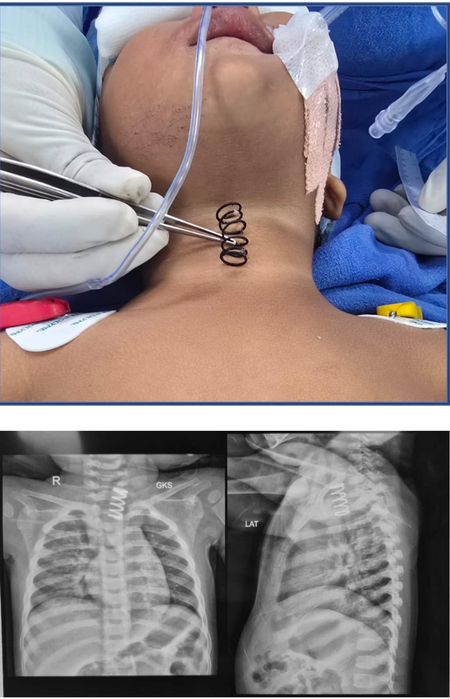

AIIMS doctors remove 2-inch-long metal spring from 14-month-old’s food pipe

New Delhi, Feb 5: Doctors at AII India Institute of Medical Sciences successfully performed a complex medical procedure to save the life of a 14-month-old girl who had swallowed a 2-inch-long metal spring, it said on Thursday.

The metal spring stuck in the oesophagus, also known as the food pipe, was successfully removed after an endoscopic surgery, AIIMS said in an official statement. he child, a resident of Yamunanagar, was brought to the hospital after suffering from continuous vomiting for about a week and not eating for two days. “During the examination, an X-ray revealed a large metal spring lodged in the upper part of the child’s oesophagus,” AIIMS said, “with ulcerations extending along the mucosa”.

“The spring was stuck on the upper part of the food pipe. And the thickness of the spring was much more than the normal spring, which we see in our pens. It was approximately half an inch wide and at least 1.5 to 2 inches long,” Professor Dr. Vishesh Jain, from the Paediatric Surgery Department, told IANS. He noted that an attempt was made to remove it endoscopically at a private hospital in Dehradun, but due to swelling and lesions in the oesophagus, the procedure was deemed risky, and the child was immediately referred to AIIMS. Jain and his team used advanced endoscopic techniques in the operating room.

The spring was carefully rotated and removed, preventing any perforation, the statement said. “After the surgery, the child’s condition improved rapidly, and she was started on oral feeding the next day,” AIIMS said. Jain advised parents to keep items such as springs, batteries, coins, and small toy parts out of reach of young children, as swallowing them can be fatal. He also said that if parents see a baby swallow something, they should take the baby to a doctor immediately so the doctor can assess the size of the object and decide on the proper treatment.